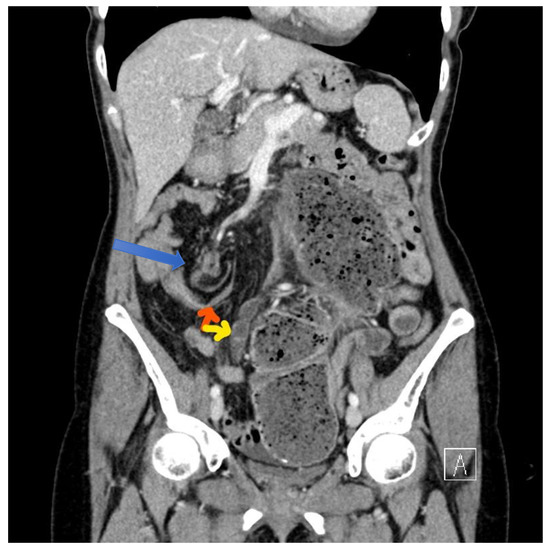

4.4.2. Computerised Tomography (CT) Scan

| CT Abdomen and pelvis | 15 | One patient operated without CT. |

| CV not described | 1 | |

| CV correctly identified | 14 (93.3%) | |

| Caecal diameter >10 cm | 10 (67%) | |

| Whirl sign | 12 (80%) | |

| Split-wall sign | 13 (86.6%) | |

| X-marks-the-spot sign | 14 (93.3%) | |

| Double transition point | 13 (86.6%) | |

| Ileocaecal twist | 13 (86.6%) | |

| Central appendix | 11 (73.3%) |